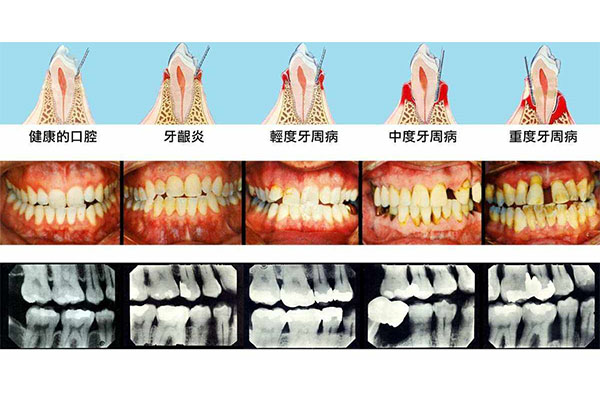

中老年人缺牙的原因多种多样,可能是牙周病、龋齿或是意外损伤。缺牙不仅影响饮食,还可能加速邻近牙齿的松动,甚至影响整体口腔健康。活动假牙因其可摘戴的特点,成为许多缺牙患者的首选。然而,选择活动假牙时,很多人会担心佩戴后的舒适度和美观度。中老年口腔专注于为中老年缺牙患者提供个性化的解决方案,通过先进的技术和贴心的服务,确保每一步都精准到位,让您的假牙佩戴更加舒适自然。